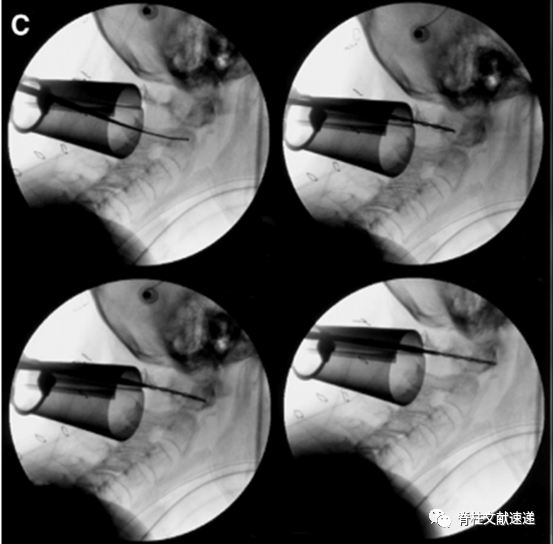

该作者首先进行了4例尸体试验,然后对2例II型齿状突骨折患者进行了微创通道下寰枢椎固定术。下图为一组术中透视影像。

上图:作出C1侧块螺钉钉道。

上图:完成寰枢椎固定。